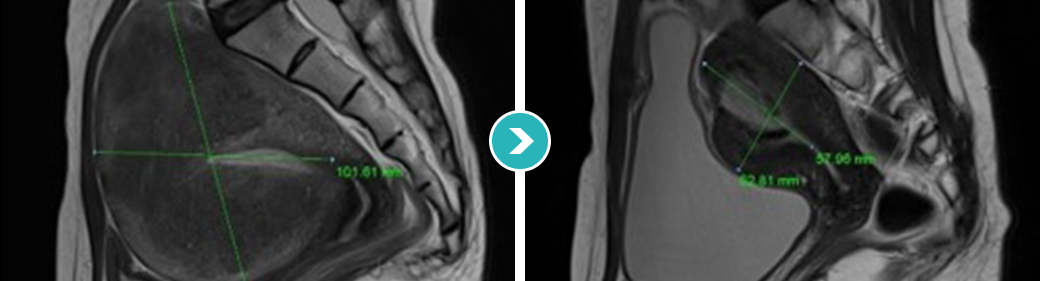

3STEP HIFU PROGRAM 2010년 부터 오직 자궁근종과 자궁선근증의 안전한 치료를 위해 전 과정MRI통합 하이푸 치료 프로그램 운영

시술 전 악성화 병변으로의 변화의 가능성 확인 및 숨어있는

악성 병변을 분석하는 MRI 촬영

시술과정 초음파영상과 MRI영상 콜라보 모니터링

시술 후 하이푸 치료 브리핑 및 객관적 평가

MRI촬영으로 자궁근종의 상태(위치, 개수, 크기, 모양 등), 자궁근종의 혈액공급 및 혈류,

자궁근종과 인접한 주요장기 및 구조, 초음파 발사경로의 확보 등을 분석함. 또한, 정밀초음파는 제거할 자궁근종의 개수, 자궁근종의 치료 슬라이스 수와

각 슬라이스의 체적, 근종제거마진, 근종과 인접한 장기와의 상관관계 등을 분석합니다.

전사적으로 시행함으로써 하이푸 시술의 안전도와 치료효과를 높이는 통합 MRI하이푸 프로그램입니다.

시술 전 MRI검사 결과를 바탕으로 자궁근종이나

자궁선근증 등 종양의 위치, 크기, 모양 등 정확하게 파악